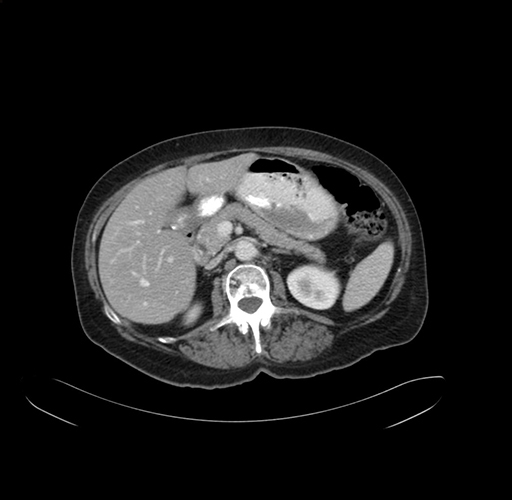

Pre-Chemo: Axial Venous